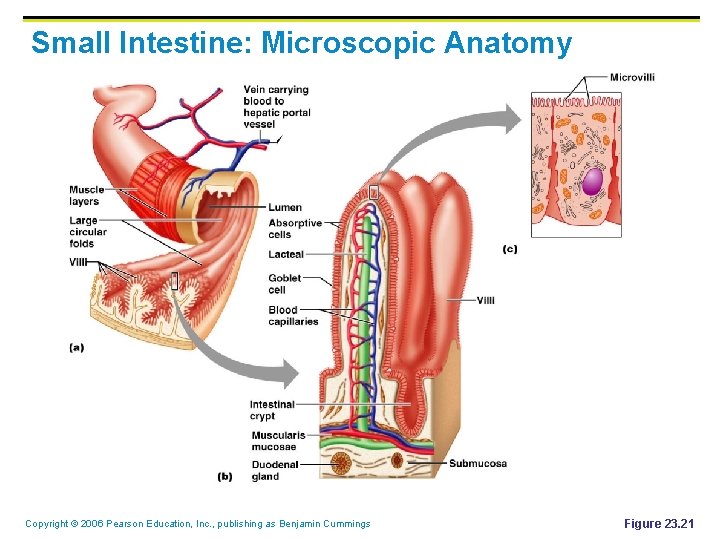

Small Intestine: Gross Anatomy § § Has three subdivisions: duodenum, jejunum, and ileum Structural modifications increase surface area: § Villi § Microvilli Copyright © 2006 Pearson Education, Inc. , publishing as Benjamin Cummings

Small Intestine: Microscopic Anatomy Copyright © 2006 Pearson Education, Inc. , publishing as Benjamin Cummings Figure 23. 21

Functions of Small Intestine: 1) Chemical digestion & 2) Absorption of nutrients into blood § Intestinal juice secreted by intestinal glands in response to distension (food entering the area) § § § Slightly alkaline and isotonic with blood plasma The majority of chemical digestion occurs in the duodenum Absorption occurs in the jejunum & ileum Copyright © 2006 Pearson Education, Inc. , publishing as Benjamin Cummings